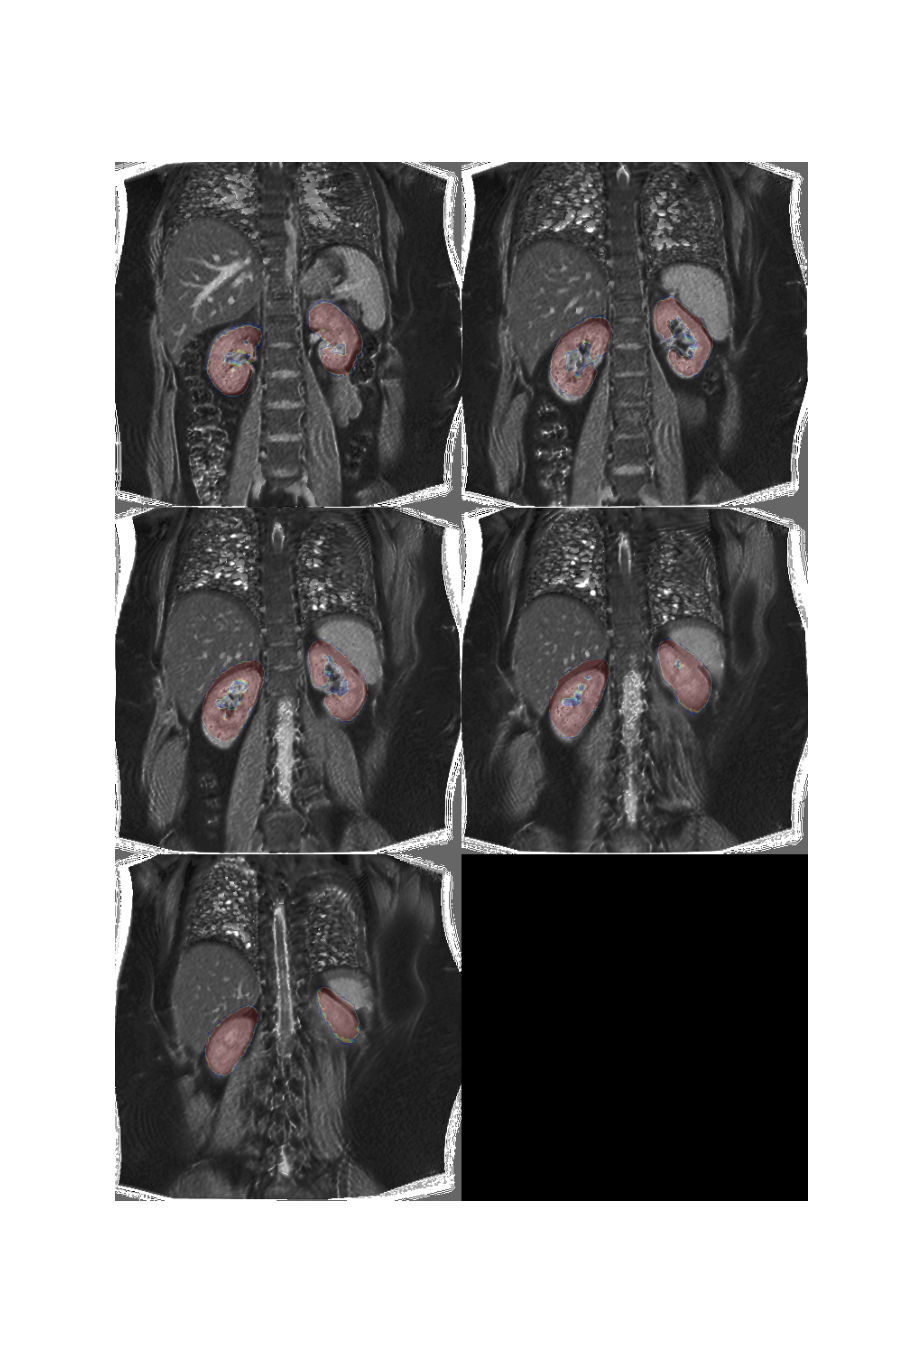

If we overlay the mask on the volume, we clearly see the misalignment due to different breath holding positions:

plt.overlay_2d(multislice, bk)

If we overlay the mask on the new volume, we can see that the misalignment is significantly reduced but some imperfections still remain.

Plot the result

plt.overlay_2d(align_lk, lk, title='Left kidney alignment')

plt.overlay_2d(align_rk, rk, title='Right kidney alignment')